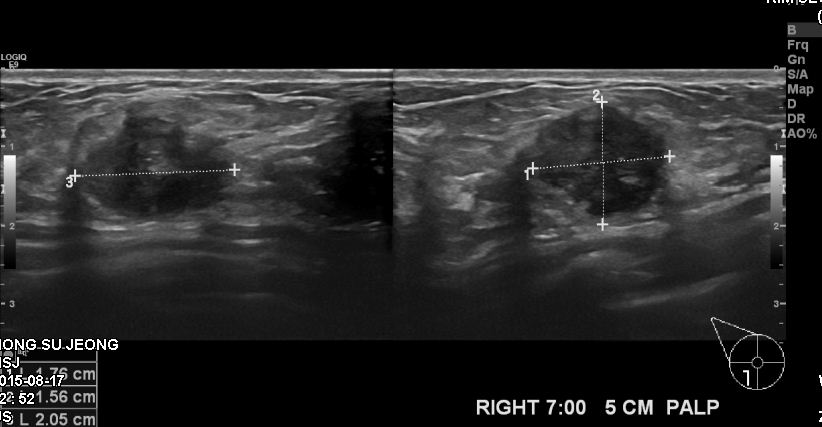

상기환자 40대 여자분으로 한달전에 만져지는 멍우리 발견하여 본원에서 우측 7시방향

조직검사 시행한후 침윤성 유관암으로 진단되셨습니다.